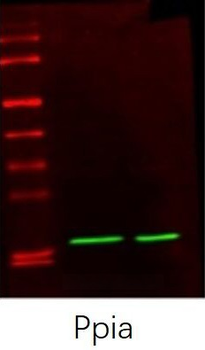

10 μg, 100 μgCYPA Rabbit Polyclonal Antibody [orb100498]

FC, IF, IHC-Fr, IHC-P, WB

Bovine, Canine, Porcine, Rabbit

Human, Mouse, Rat

Rabbit

Polyclonal

Unconjugated